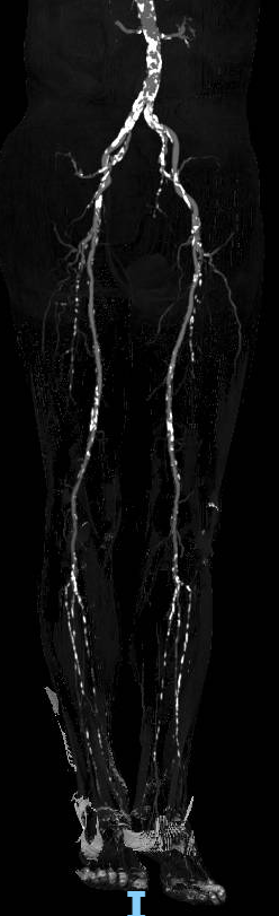

现病史:患者双下肢间歇性跛行5年余,跛距300米。后跛行症状加重伴双足发凉发麻跛距缩短至50米,右侧重、无静息痛、溃疡。下肢CTA提示:双侧股浅动脉重度狭窄近闭塞、右侧腘动脉重度狭窄

步进造影:股浅动脉起始重度狭窄、中段重度狭窄,腘动脉远端重度狭窄、胫前动脉、胫后动脉闭塞

步进造影配合血管腔内超声诊断导管提示:股浅动脉全程、腘动脉、胫腓干动脉血流通畅,未见明显夹层、造影剂外溢,远端未见栓塞,膝下动脉如前。

腘动脉压力:90mmHg,比值0.73(原比值 0.54)

足背动脉压力85mmHg,比值0.69(原比值 0.45)

腘动脉压力:120mmHg,比值0.98 (原比值 0.65)

胫后动脉压力:118mmHg,比值0.96(原比值 0.54)

足背动脉压力:115mmHg,比值0.93(原比值 0.59)